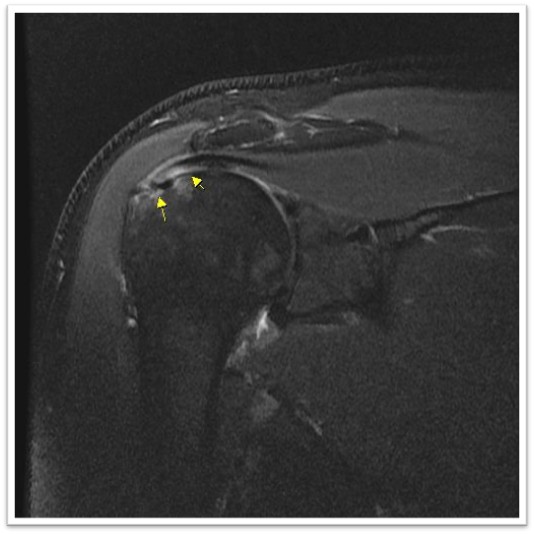

MRI와 초음파를 다시 검토했습니다.

회전근개 극상건의 관절면측(articular-side) 부분파열.

관절면측(articular-side) 파열은 회전근개의 아래쪽, 즉 관절에 면한 부분이 손상된 것입니다.